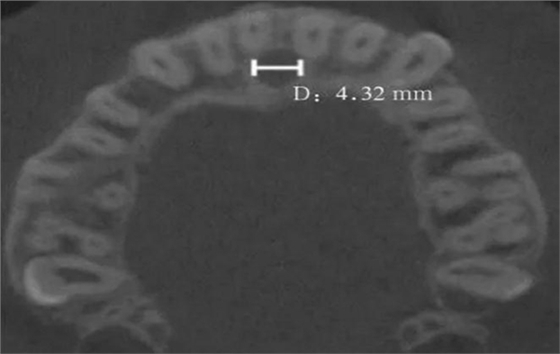

(2)水平面:以第一次觀察到完整的切牙孔形態(tài)的平面作為觀測(cè)平面(圖4)。

D:切牙孔橫徑。

圖 4 切牙孔橫徑測(cè)量方法

Fig 4 Measurements oftransverse diameter of nasopalatine canal

本研究在可重復(fù)的測(cè)量方式及較大的樣本量的基礎(chǔ)上進(jìn)行分析,希望取得更為準(zhǔn)確、科學(xué)的結(jié)果。筆者通過(guò)水平面和正中矢狀面對(duì)鼻腭管進(jìn)行評(píng)估,得出鼻腭管矢狀面直徑平均值為(3.37±1.58)mm,小于Mraiwa等[5]的測(cè)量結(jié)果4.6 mm;大于T?züm等[6]的測(cè)量結(jié)果2.59 mm;與Liang等[3]的測(cè)量結(jié)果3.4 mm、Thakur等[7]的測(cè)量結(jié)果3.61 mm和王智等[8]的測(cè)量結(jié)果3.41 mm相近。鼻腭管平均長(zhǎng)度為(13.58±2.22)mm,大于Song等[9]的測(cè)量結(jié)果12.0 mm;小于AL-Amery等[10]的測(cè)量結(jié)果16.33 mm;而與Fernández-Alonso等[1]的測(cè)量結(jié)果(12.34±2.79)mm,以及Zhou等[11]的測(cè)量結(jié)果(12.80±2.17)mm相近。唇側(cè)骨厚度的平均值為(7.63±1.5)mm,與AL-Amery等[10]的測(cè)量結(jié)果7.54 mm、T?züm等[6]的測(cè)量結(jié)果(7.17±1.49)mm、Mraiwa等[5]的測(cè)量結(jié)果(7.4±2.6)mm均相近。在水平面測(cè)量中,一些研究[8]對(duì)于鼻腭管矢徑和橫徑的長(zhǎng)短存在爭(zhēng)議,筆者認(rèn)為該結(jié)果的差異可能是由水平面切牙孔形狀的變異性及對(duì)有骨突和不規(guī)則切牙孔測(cè)量方法的不確定性造成的。為避免該誤差,本研究只測(cè)量切牙孔開(kāi)口為1個(gè)且形狀為圓形的病例,測(cè)得水平面鼻腭管直徑為(3.45±0.95)mm,鼻腭管橫徑與矢徑差異無(wú)統(tǒng)計(jì)學(xué)意義。